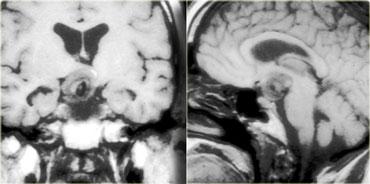

Phình động mạch và U màng não

Một trong những chẩn đoán phân biệt khó nhất trên CT là phình động mạch so với u màng não.

Ở bệnh nhân này có một khối lớn ở bên phải, có thể xuất phát từ màng não hoặc xoang hang.

Trên CT, không thể phân biệt được liệu khối này là túi phình động mạch hay u màng não.

Đây là hình ảnh MRI của cùng bệnh nhân.

Khối có tín hiệu chủ yếu là đen và có một xảo ảnh dòng chảy lớn chạy theo hướng mã hóa pha.

Các đặc điểm này tương ứng với dòng máu chảy nhanh, do đó khối này phải là một túi phình động mạch.

Hình chụp mạch máu của cùng bệnh nhân.

Hình ảnh cho thấy dòng chảy trong túi phình không phải là dòng chảy tầng (laminar), mà là dòng chảy xoáy, lấp đầy dần lòng túi phình bằng thuốc cản quang.